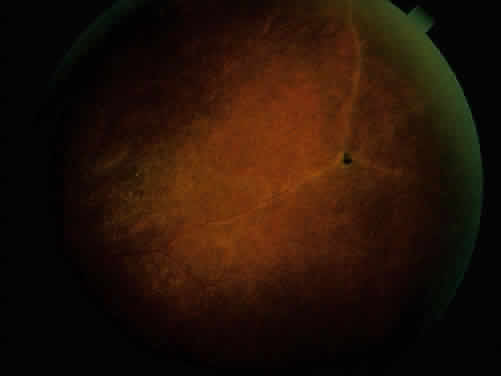

Ankylosing spondylitis is distinctly different from rheumatoid arthritis, although earlier literature did not make this distinction. The sacroiliac joint is usually the most easily visible area of involvement and is best seen in oblique views on radiography of the sacroiliac joint as periarticular sclerosis and irregular loss of the joint space. These patients are seronegative for rheumatoid factor and may have an elevated erythrocyte sedimentation rate.3,6 The presence of HLA-B27 antigen in 90% to 95% of white patients and 50% of black patients with ankylosing spondylitis is well documented, and the genetic predisposition to this disease has been recognized for many years. The relationship, however, is still incompletely understood at this point. HLA-B27 antigen is present in 6% to 14% of the white American population and 3% to 4% of the black American population. It is clear that people with this HLA type are at greater risk of developing one of the spondyloarthropathies, particularly ankylosing spondylitis, but as yet poorly defined environmental factors must be involved in triggering the development of the disease process.3,8 The development of acute iridocyclitis is even more strongly correlated with HLA-B27 antigen than is its association with joint changes. Of patients with HLA-B27 antigen, 20% to 25% will develop symptoms or radiographic evidence of spondylitis at some time in their life, and milder forms of the disease are commonly not diagnosed but believed to be due to back “strain” or injury. The incidence of clinical spondylitis is about equal between men and women, but the disease tends to be milder and more difficult to diagnose in women; its prevalence appears to approach 2% in those in the North American population who are HLA-B27 positive and who have been studied. The mechanism of how HLA-B27 antigen is involved in this disease process is unclear. HLA determinants are located on chromosome 6. These determine cell surface markers that enable the immune system to recognize each cell as self. One theory that has been advanced suggests that the HLA-B27 antigen may be similar to antigens of the cell wall of certain exogenous agents or may be changed by the agents in a manner whereby the immune system has difficulty recognizing or responding appropriately to the agent or the altered HLA-B27 antigen. In one study, patients with ankylosing spondylitis had lower in vitro responsiveness of lymphocytes to Klebsiella antigens than HLA-B27-positive and HLA-B27-negative controls.9 Antisera to certain isolates of Klebsiella lysed the lymphocytes of HLA-B27-positive patients with ankylosing spondylitis, but not the lymphocytes of HLA-B27-positive or HLA-B27-negative controls. This suggests that perhaps some Klebsiella antigens cross-react with a gene product closely associated with HLA-B27 or a Klebsiella-modified B27 antigen in patients with ankylosing spondylitis. Cross-reacting antigens have been identified in HLA-B27 and Klebsiella, Shigella, and Yersinia.10 The role of Klebsiella has not been clarified, and no other agent has been substantiated with respect to ankylosing spondylitis. Chlamydia has been suggested in some cases of Reiter's syndrome, especially in instances of nonspecific urethritis.11–13 Shigella, Salmonella, and Yersinia have been involved in clinical epidemics of postinfectious arthropathies.14 Additional theories involve HLA-B27 linkage with a specific immune response gene that predisposes patients to the disease, perhaps making them more susceptible to infection. The role of these factors remains to be clarified. The acute iridocyclitis associated with ankylosing spondylitis is characterized by rapid onset of pain, photophobia, and blurred vision. Conjunctival, episcleral, and scleral injection and edema are seen. Poorly defined keratic precipitates are seen in the lower half of the corneal endothelium, and the anterior chamber has heavy flare that may be uneven. If the process is severe, there may be clot formation in the pupil space.15,16 Cells in the anterior chamber may be so numerous that hypopyon will occur. Glaucoma can result from anterior chamber reaction blockage of the angle in the acute phase of inflammation and from pupil block from synechiae. Synechiae form early and, if not broken, will form lasting adhesions. Mydriatic and cycloplegic therapy is needed early in treatment. Spillover of inflammatory cells and inflammatory debris into the vitreous may occur, and the presence of disc blurring and macular edema is sometimes observed. This is sometimes also associated with hypotony. Posterior subcapsular cataracts and diffuse lens clouding are seen with severe prolonged episodes and repeated acute recurrences.15,16 The typical episode lasts from 2 to 6 weeks. Aggressive suppression of the inflammatory reaction with topical corticosteroids is usually sufficient and reduces tissue damage, if an early intensive schedule is used, rather than increasing the drop schedule as the reaction increases. These patients may need to be seen daily when they are acutely active and may need to be seen every 2 to 3 days until the process is stable or clearly resolving. Treatment must be continued for several weeks as the process is resolving or reactivation will occur. Oral corticosteroids can be given for short periods of time. Some patients experience elevation of intraocular pressure with corticosteroid therapy, particularly as the eye improves and the ciliary body is again more able to produce aqueous humor. The long-acting effects of periocluar injection of corticosteroids may become a more serious problem with persistent corticosteroid-induced glaucoma than the episode of acute iridocyclitis that was being treated. Frequent episodes of recurrent iridocyclitis may cause significant disability that results in loss of work, discomfort, and structural damage to the eye. These patients may benefit from longer term treatment with oral nonsteroidal anti-inflammatory agents, such as indomethacin or naproxen. These medications may help to reduce the severity and frequency of recurrences, but the pain-decreasing effects of these medications may make it more difficult for the patient to recognize an acute recurrence of the iridocyclitis. Patients should be examined for exacerbations of the inflammation if they note any change in vision, even minor symptoms. REITER'S SYNDROME OR POSTINFECTIOUS REACTIVE ARTHRITIS Reiter's syndrome is a clinical syndrome usually described as arthritis, conjunctivitis, or iridocyclitis and nonbacterial urethritis or cervicitis. A better definition may be needed, because not only may these not all be present, but also dysentery and mucocutaneous disease with balanitis, oral ulceration, or keratoderma blennorrhagicum may be part of the clinical picture. Enthesopathy of the plantar fascia or Achilles tendon is also suggestive of Reiter's syndrome. It is more commonly identified in males, but may be more frequent in females than previously thought.14 The incidence reported by Noer17 in US Navy personnel over a 10-year period was 4 in 100,000 men per year. HLA-B27-positive persons have approximately a 25% risk for Reiter's syndrome development after Shigella infection.18 Although the cause is unknown, the high correlation with the presence of HLA-B27 (75%)19 is clearly recognized. The previous discussion in the section on spondyloarthropathies concerning this HLA-B27 association demonstrates a genetic predisposition in a high percentage of these patients. In Reiter's syndrome, infectious agents are suggested by reports of clinically indistinguishable acute disease after epidemic dysentery and sexually transmitted nongonococcal urethritis thought to be due to Chlamydia20 or possibly Mycoplasma (Ureaplasma urealyticum).21,22 Large epidemics of dysentery have been linked to multiple occurrences of arthritis, urethritis, and iridocyclitis.17,23 Shigella, Campylobacter, Salmonella, and Yersinia have all been implicated.24 Microbial antigens have been identified in the synovium after infectious with Chlamydia, Yersinia, and Salmonella.25–27 Salmonella typhimurium is a frequently associated Salmonella pathogen causing reactive arthritis. This seronegative arthritis usually involves larger joints and the weight-bearing joints of the lower extremities. The knees and ankles are most frequently involved, with redness and diffuse swelling. Multiple joint involvement is usual. Periostitis and tendinitis may occur, especially involving the Achilles tendon, producing heel pain. Sacroiliac radiographic changes are present in up to 32% of patients.14 Children may be affected rarely.28 Reiter's syndrome tends to affect young adults in the range of 16 to 40 years of age. The diagnosis is sometimes hard to establish because the urethritis or cervicitis may be forgotten or suppressed and the enteritis and other symptoms may have been mild or not identified as abnormal. If a urethritis or cervicitis is present, cultures should be considered to make sure no treatable organism is present, such as gonococcus. Serologic testing for syphilis will help to rule out this sometimes-associated venereal problem. Low back pain due to insertional tendinitis and sacroiliitis is common. The dermal lesions typified by keratoderma blennorrhagicum, described as a hyperkeratotic erythematous dermatitis resembling pustular psoriasis, may not be present until later in the disease. It usually involves the hands and feet but may involve other areas. Superficial ulcers of the mucous membranes are frequent.29 Enteritis is usually a prolonged diarrheal episode with frequent passage of bloody, loose stools, but it may be a 24-hour episode of increased bowel activity.29 The conjunctivitis is usually described as mucopurulent and may be sterile. It may be accompanied by an iridocyclitis, episcleritis, or scleritis. Punctate and subepithelial corneal involvement has been reported. The iridocyclitis may be the presenting ocular manifestation. Recurrences are usually associated with an acute iridocyclitis, which is of rapid onset with conjunctival and episcleral edema and injection. The corneal endothelium has cellular debris and poorly defined, small-sized to medium-sized keratic precipitates.30 Heavy flare and cells and a very early tendency toward formation of posterior synechiae is characteristic, more so than in most other forms of acute iridocyclitis (Figs. 1, 2, and 3). Even the most aggressive pupil dilation management is sometimes inadequate for preventing synechiae. A peripheral iridectomy may be necessary to prevent iris bombé and angle closure if the synechiae cannot be broken enough to establish an opening for aqueous through the pupil (Fig. 4). The heavy flare is sometimes so plasmoid that cells are immobile and a fibrinlike clot may be seen in the pupil opening as the inflammation resolves. Cells and inflammatory debris may be seen in the vitreous, and blurring of the disc margins and macular edema may occur with severe or prolonged episodes. Lens clouding and posterior subcapsular cataracts occur with prolonged or repeated episodes. Hypotony can occur after a severe or prolonged course and may persist after resolution. Occasionally, secondary glaucoma may occur, owing to the anterior chamber reaction, in which case it will resolve as the inflammation resolves. With repeated recurrences, damage to the trabecular meshwork may occur, and prolonged recalcitrant glaucoma may result that may be poorly responsive to any medical or surgical management. This can be a serious factor in permanent visual loss with this type of iridocyclitis.15,16,30,31

Ocular inflammatory changes include conjunctivitis, episcleritis, keratitis, acute and chronic iridocyclitis, and posterior changes as well.38–43 The acute iridocyclitis is milder and frequently not accompanied by as much pain, photophobia, and redness as in the acute iridocyclitis associated with other spondyloarthropathies. Mild injection of the conjunctival and episcleral vessels and blurred vision may be the only symptoms of an acute flare of activity. The endothelium of the cornea usually has cellular debris and poorly formed keratic precipitates in the lower cornea. The anterior chamber contains cells and moderate flare, and a protein clot is not infrequent in the pupil, with early formation of posterior synechiae (Fig. 6); however, the synechiae are usually more easily broken than in ankylosing spondylitis and Reiter's syndrome.44 Treatment with topical corticosteroids and mydriatics is usually effective. The activity of the iridocyclitis has been reported to follow the activity course of the inflammatory bowel disease. Systemic treatment of inflammatory bowel disease has been noted to help the ocular inflammation. Decreasing the systemic treatment occasionally allows ocular inflammation to become visible and requires close observation and appropriate increase in local therapy.39,44–46 Surgical resection of inflamed bowel for other medical reasons has sometimes been reported to coincide with lessening of ocular inflammation,44,46 but these observations need better evaluation.42 Posterior segment manifestations, including retinal and choroidal vascular disease, are also sometimes noted.47,48